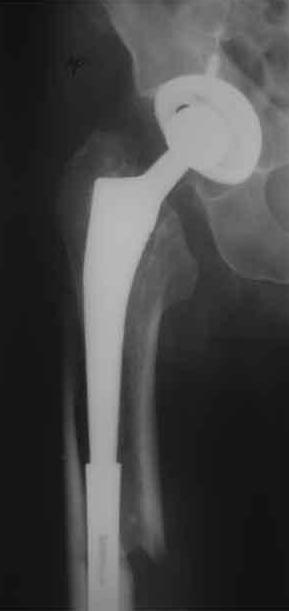

Уважаемые коллеги, продолжая дискуссию, начатую на "Вреденовских чтениях", хочу сказать, что принципиально сущестует два возможных варианта лечения.

1.Остеосинтез на ножке. Мне кажется, что применительно к этому случаю малоперспективный вариант. Синтез хорош, когда можно его выполнить в малоинвазивном исполнении и достигнуть стабильности. Действительно, если ножка б/цементной фиксации после этого не будет иметь фиксации, то ревизия не будет иметь проблем. В представленном случае стабильность синтеза сомнительная, а проведение доп.иммобилизации приведет к контрактуре суставов.

2. Применение ножки дистальной фиксации, мы отдаем предпочтение ножке Вагнера с фиксацией проксимального отдела на ножке. Более травматичное вмешательство, но при стабильной фиксации ножки реабилитация идет в обычном режиме.

Хочется показать два подобных случая, П-ка З. 72 лет и п-т Г. 80 лет. Сразу принимаю замечание, что это были ножки цементной фиксации, просто под руками не было бесцементника.

С уважением, Р.Тихилов

Пациента удалось осмотреть недавно. Достигнутый результат сохраняется. Перелом бедра сросся. Конечность опорная и безболезненная, ходит без трости. Ножка, похоже, реинтегрировалась, как и надеялись. Снимки и фото в приложении. Комментарии приветствуются.

Надо ли что-то делать дальше, как полагаете? Убрать винты? Убрать "удлинитель ножки"? Или оставить все, как есть? Спасибо заранее.